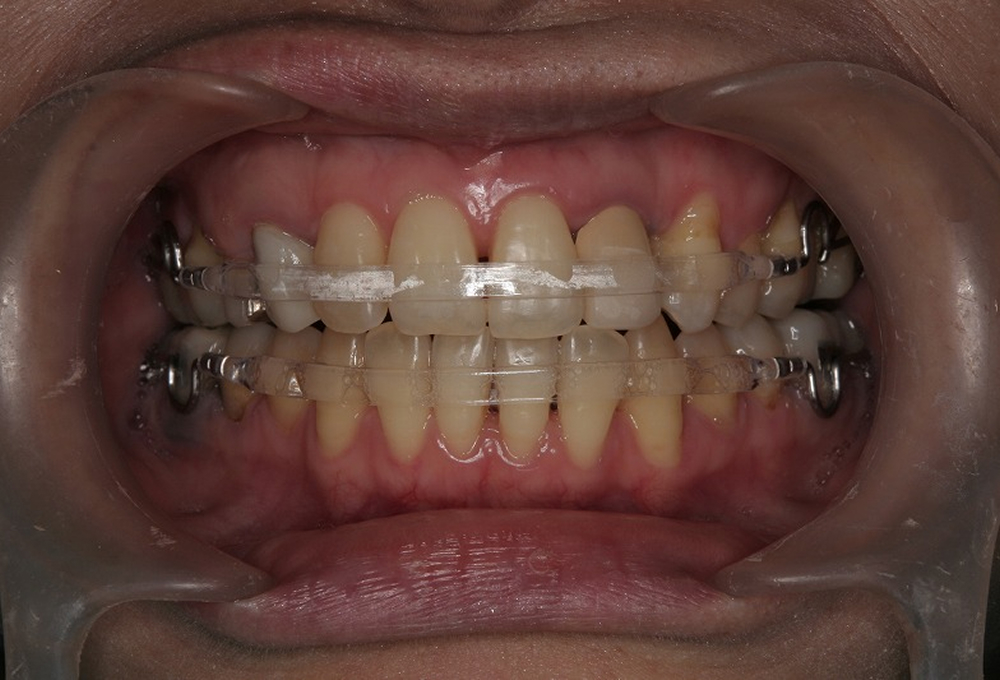

④矯正治療